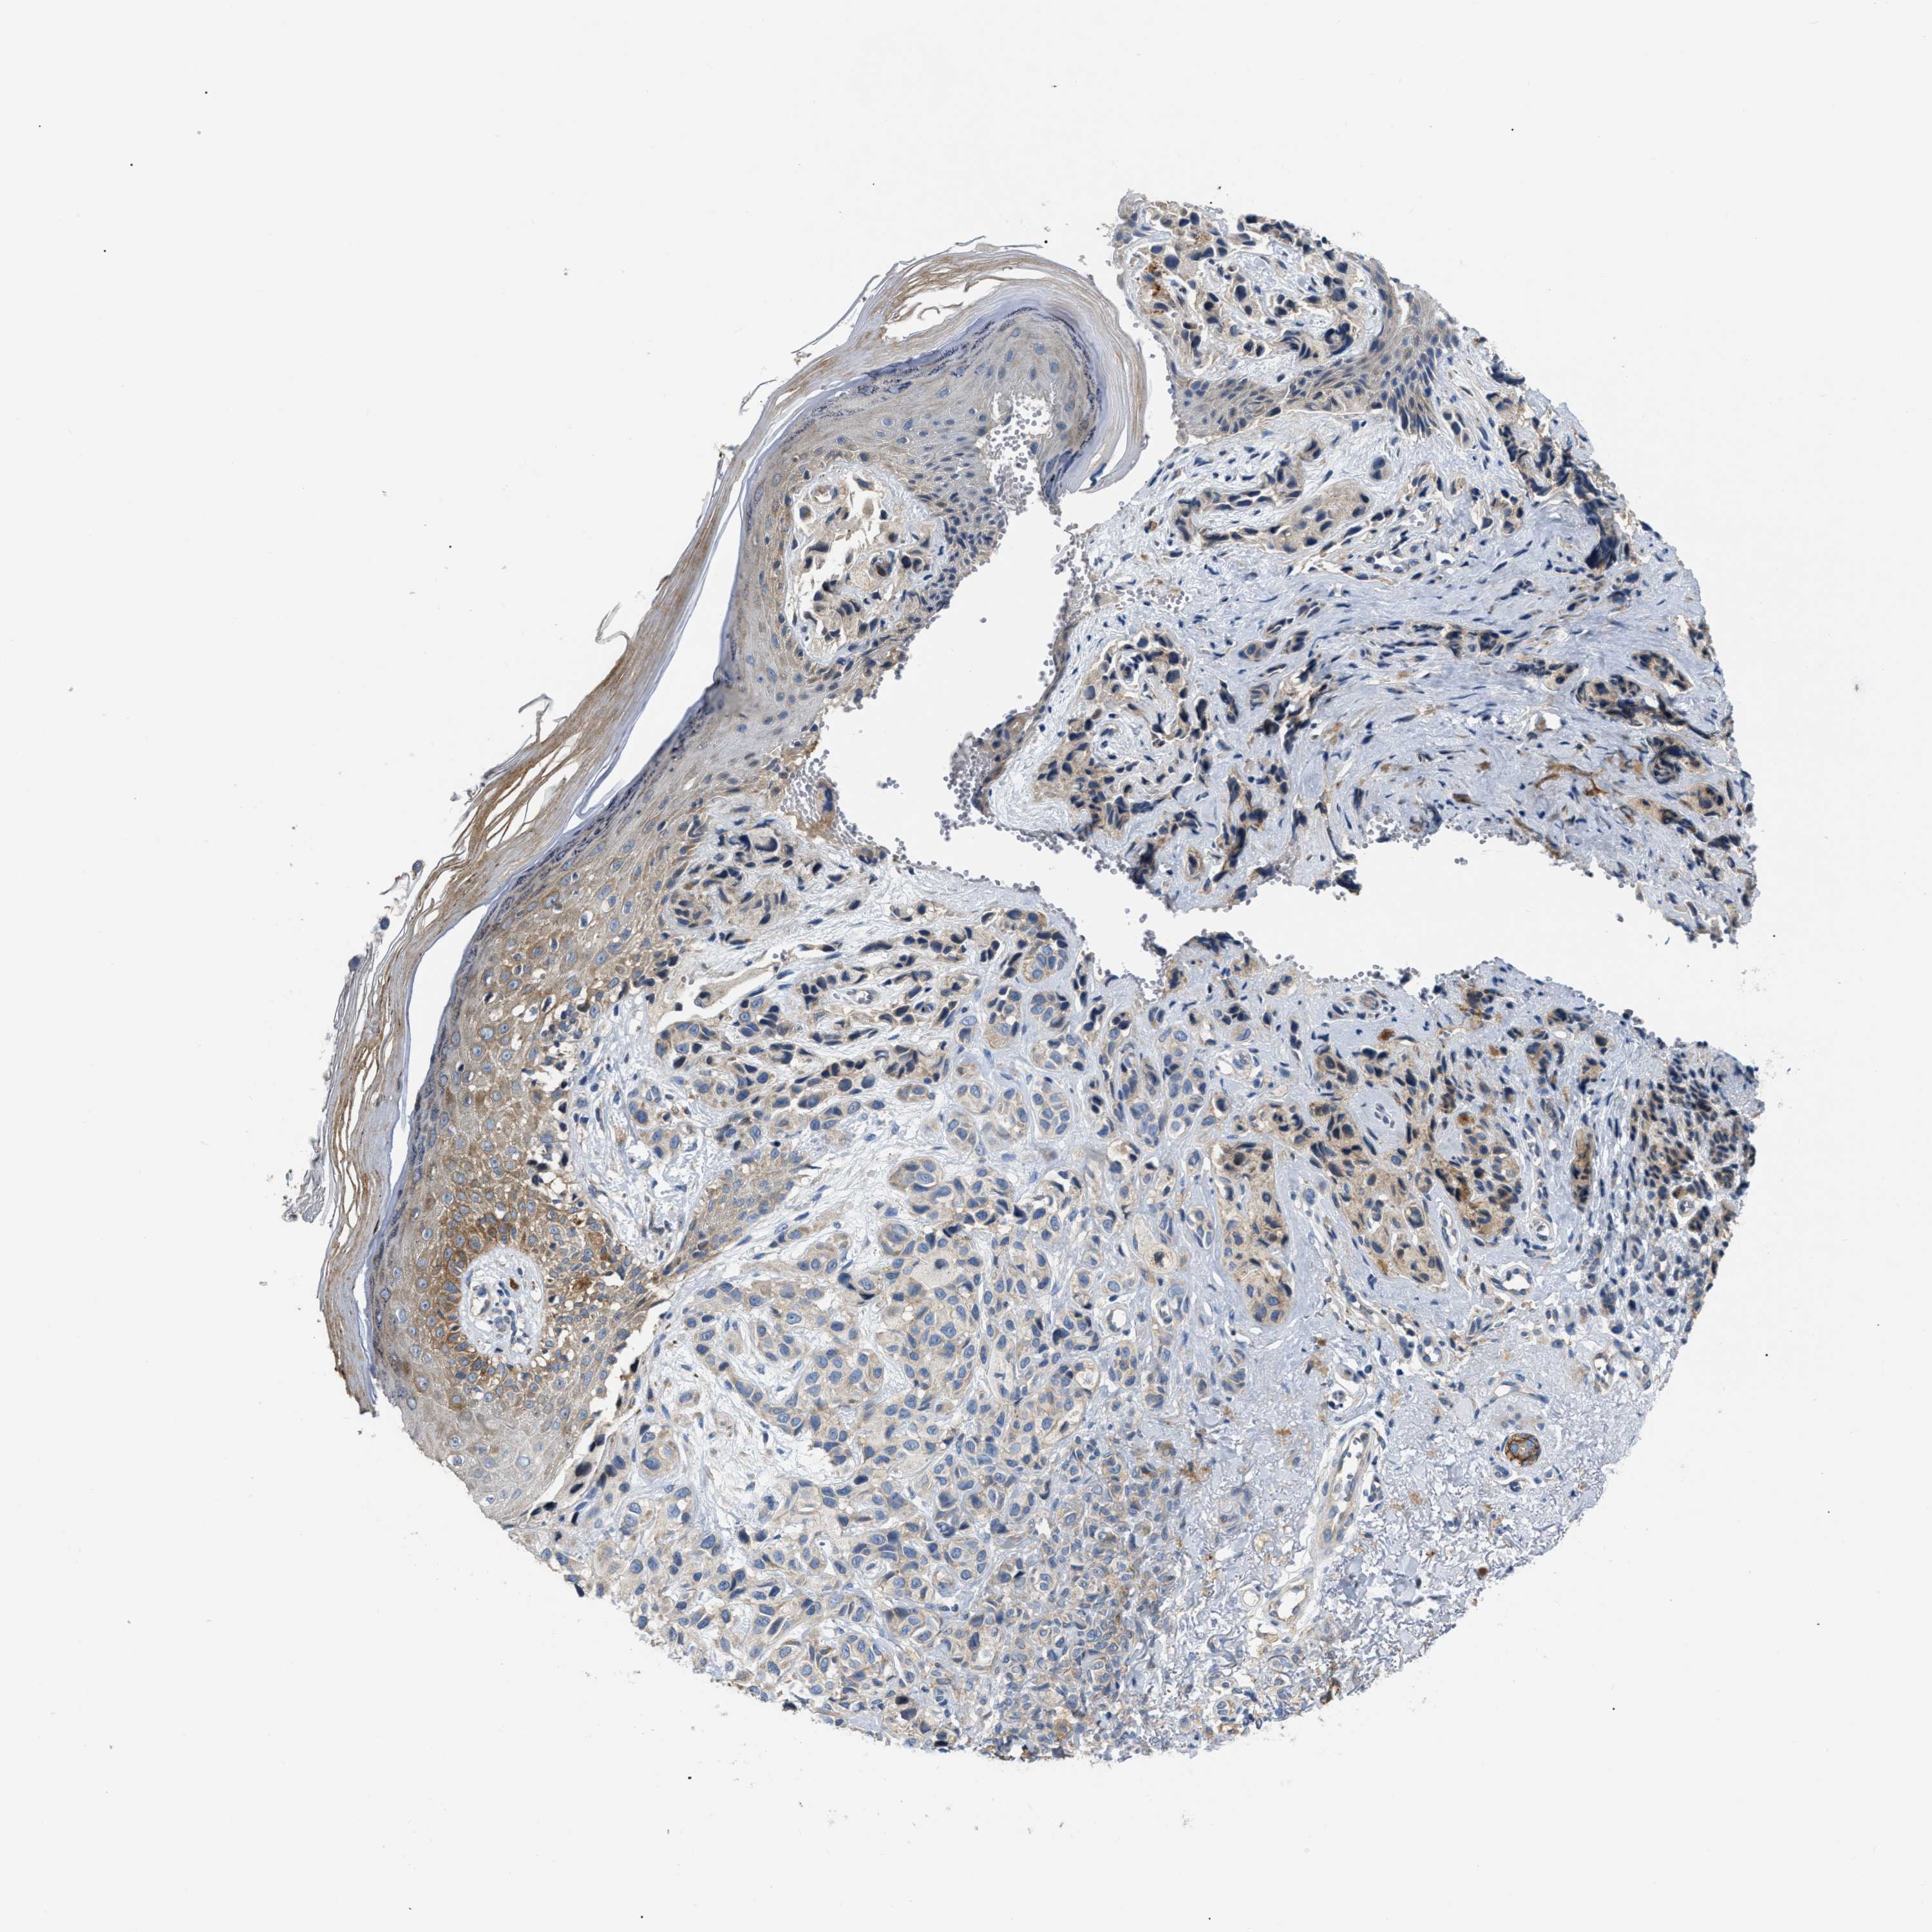

MELANOMA - Protein expressioni

A mouse-over function shows sample information and annotation data. Click on an image to view it in a full screen mode. Samples can be filtered based on level of antibody staining by selecting one or several of the following categories: high, medium, low and not detected. The assay and annotation is described here.

Note that samples used for immunohistochemistry by the Human Protein Atlas do not correspond to samples in the TCGA dataset.

Antibody stainingi

Antibody staining in the annotated cell types in the current human tissue is reported as not detected, low, medium, or high, based on conventional immunohistochemistry profiling in selected tissues. This score is based on the combination of the staining intensity and fraction of stained cells.

Each image is clickable and will lead to virtual microscopy that enables deeper exploration of all samples and also displays staining intensity scores, fraction scores and subcellular localization as well as patient and tissue information for each sample.

Antibody HPA018670

Antibody HPA019570

Staining

High

Medium

Low

Not detected

Intensity

Strong

Moderate

Weak

Negative

Quantity

>75%

75%-25%

<25%

None

Location

Nuclear

Cytoplasmic/membranous

Cytoplasmic/membranous,nuclear

Malignant melanoma, NOS

Malignant melanoma, Metastatic site